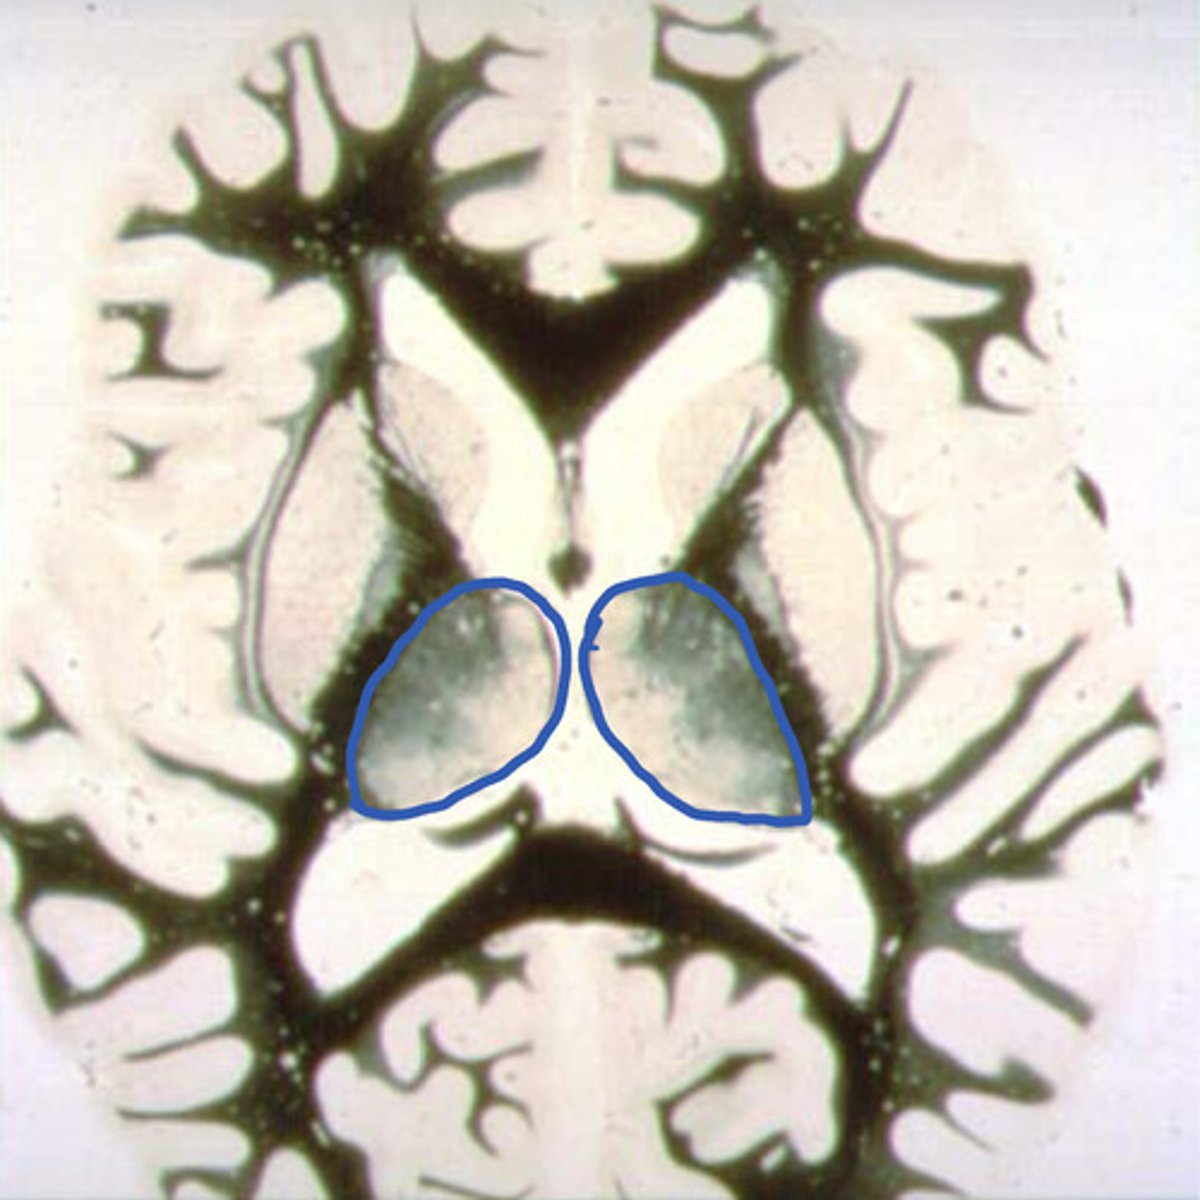

5

which is the globus pallidus?

head of the caudate nucleus

identify the structure

putamen

globus pallidus